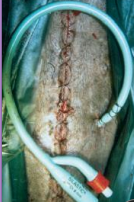

Tx: ventral midline incision, ID defect, repair, lavage, drains, catheter